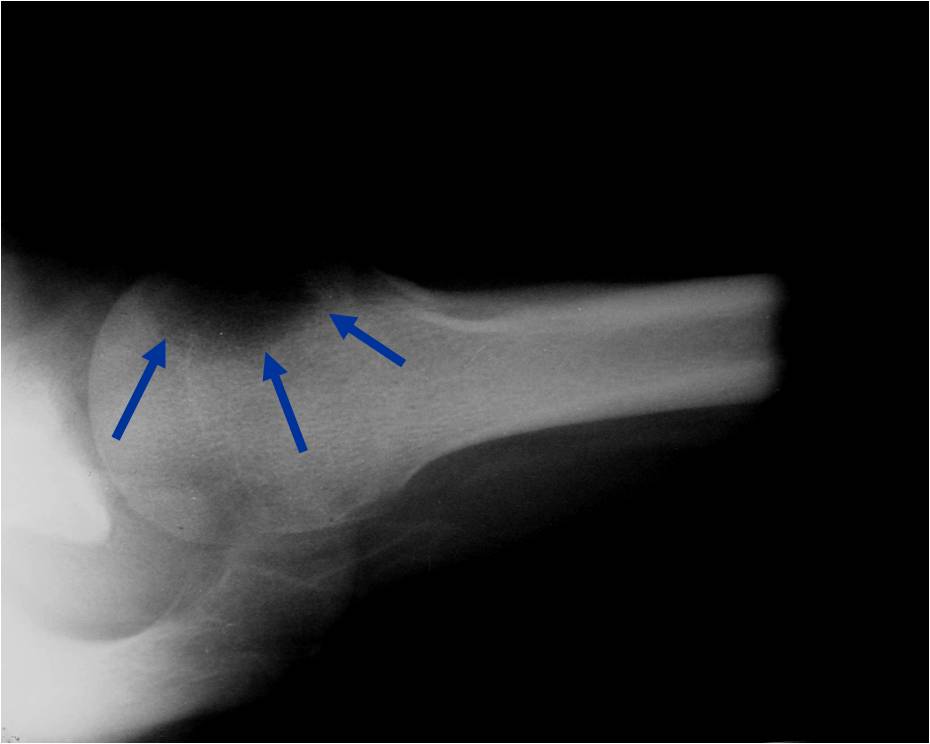

General Information Enchondroma is a benign indolent intramedullary hyaline cartilage neoplasm Accounts for 10% of all benign osseous tumors Limited growth, most lesions are less than 5 cm in maximal dimension Bones grow from a cartilaginous growth plate that...